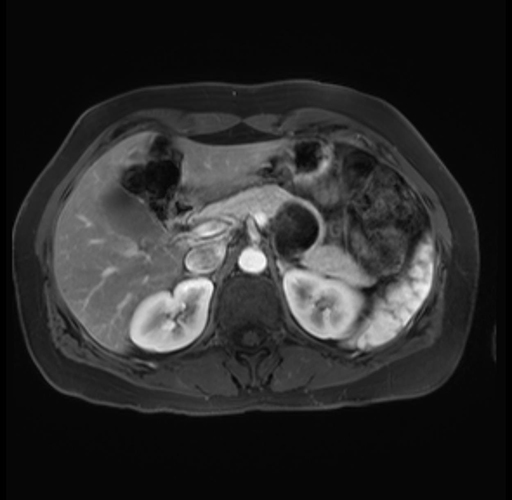

Imaging Analysis

Look through the patient's CT scan to identify any areas of concern for the necessary procedure.

Based on your CT findings, which issue(s) are present and would give reason for "planned slowing down moment(s)" in this case?